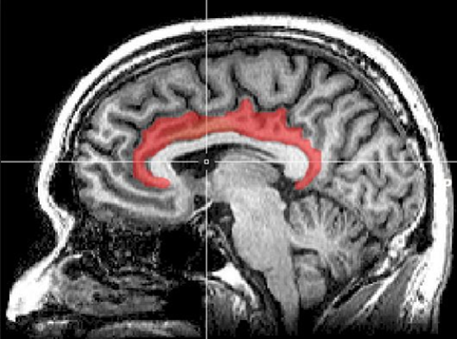

Магнитно-резонансная томография (МРТ) — ещё один вид диагностики, позволяющий идентифицировать синдром выгорания. За эмпатию, эмоциональную регуляцию и распознавание эмоций отвечает лимбическая система мозга (миндалевидное тело, гиппокамп, гипоталамус и поясная извилина). Соответственно, уменьшение активности в этих областях, отслеживаемое на МРТ, может служить маркером выгорания.

Поясная извилина — часть лимбической системы (снимок с МРТ)